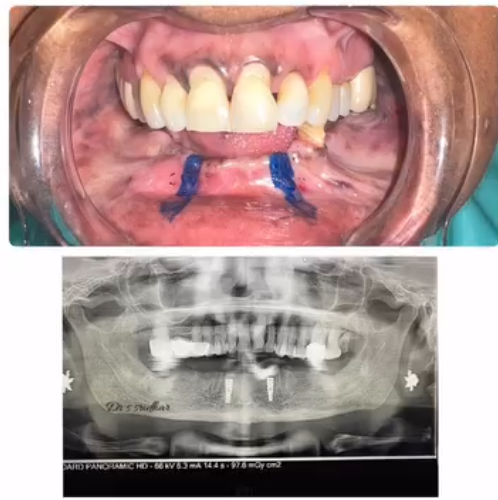

Diagnosis & X-ray – To identify the infected area.

Dental Implants A permanent solution for missing teeth. Implants act as artificial tooth roots and provide superior stability and aesthetics.

High-end digital X-rays and rotary endodontics